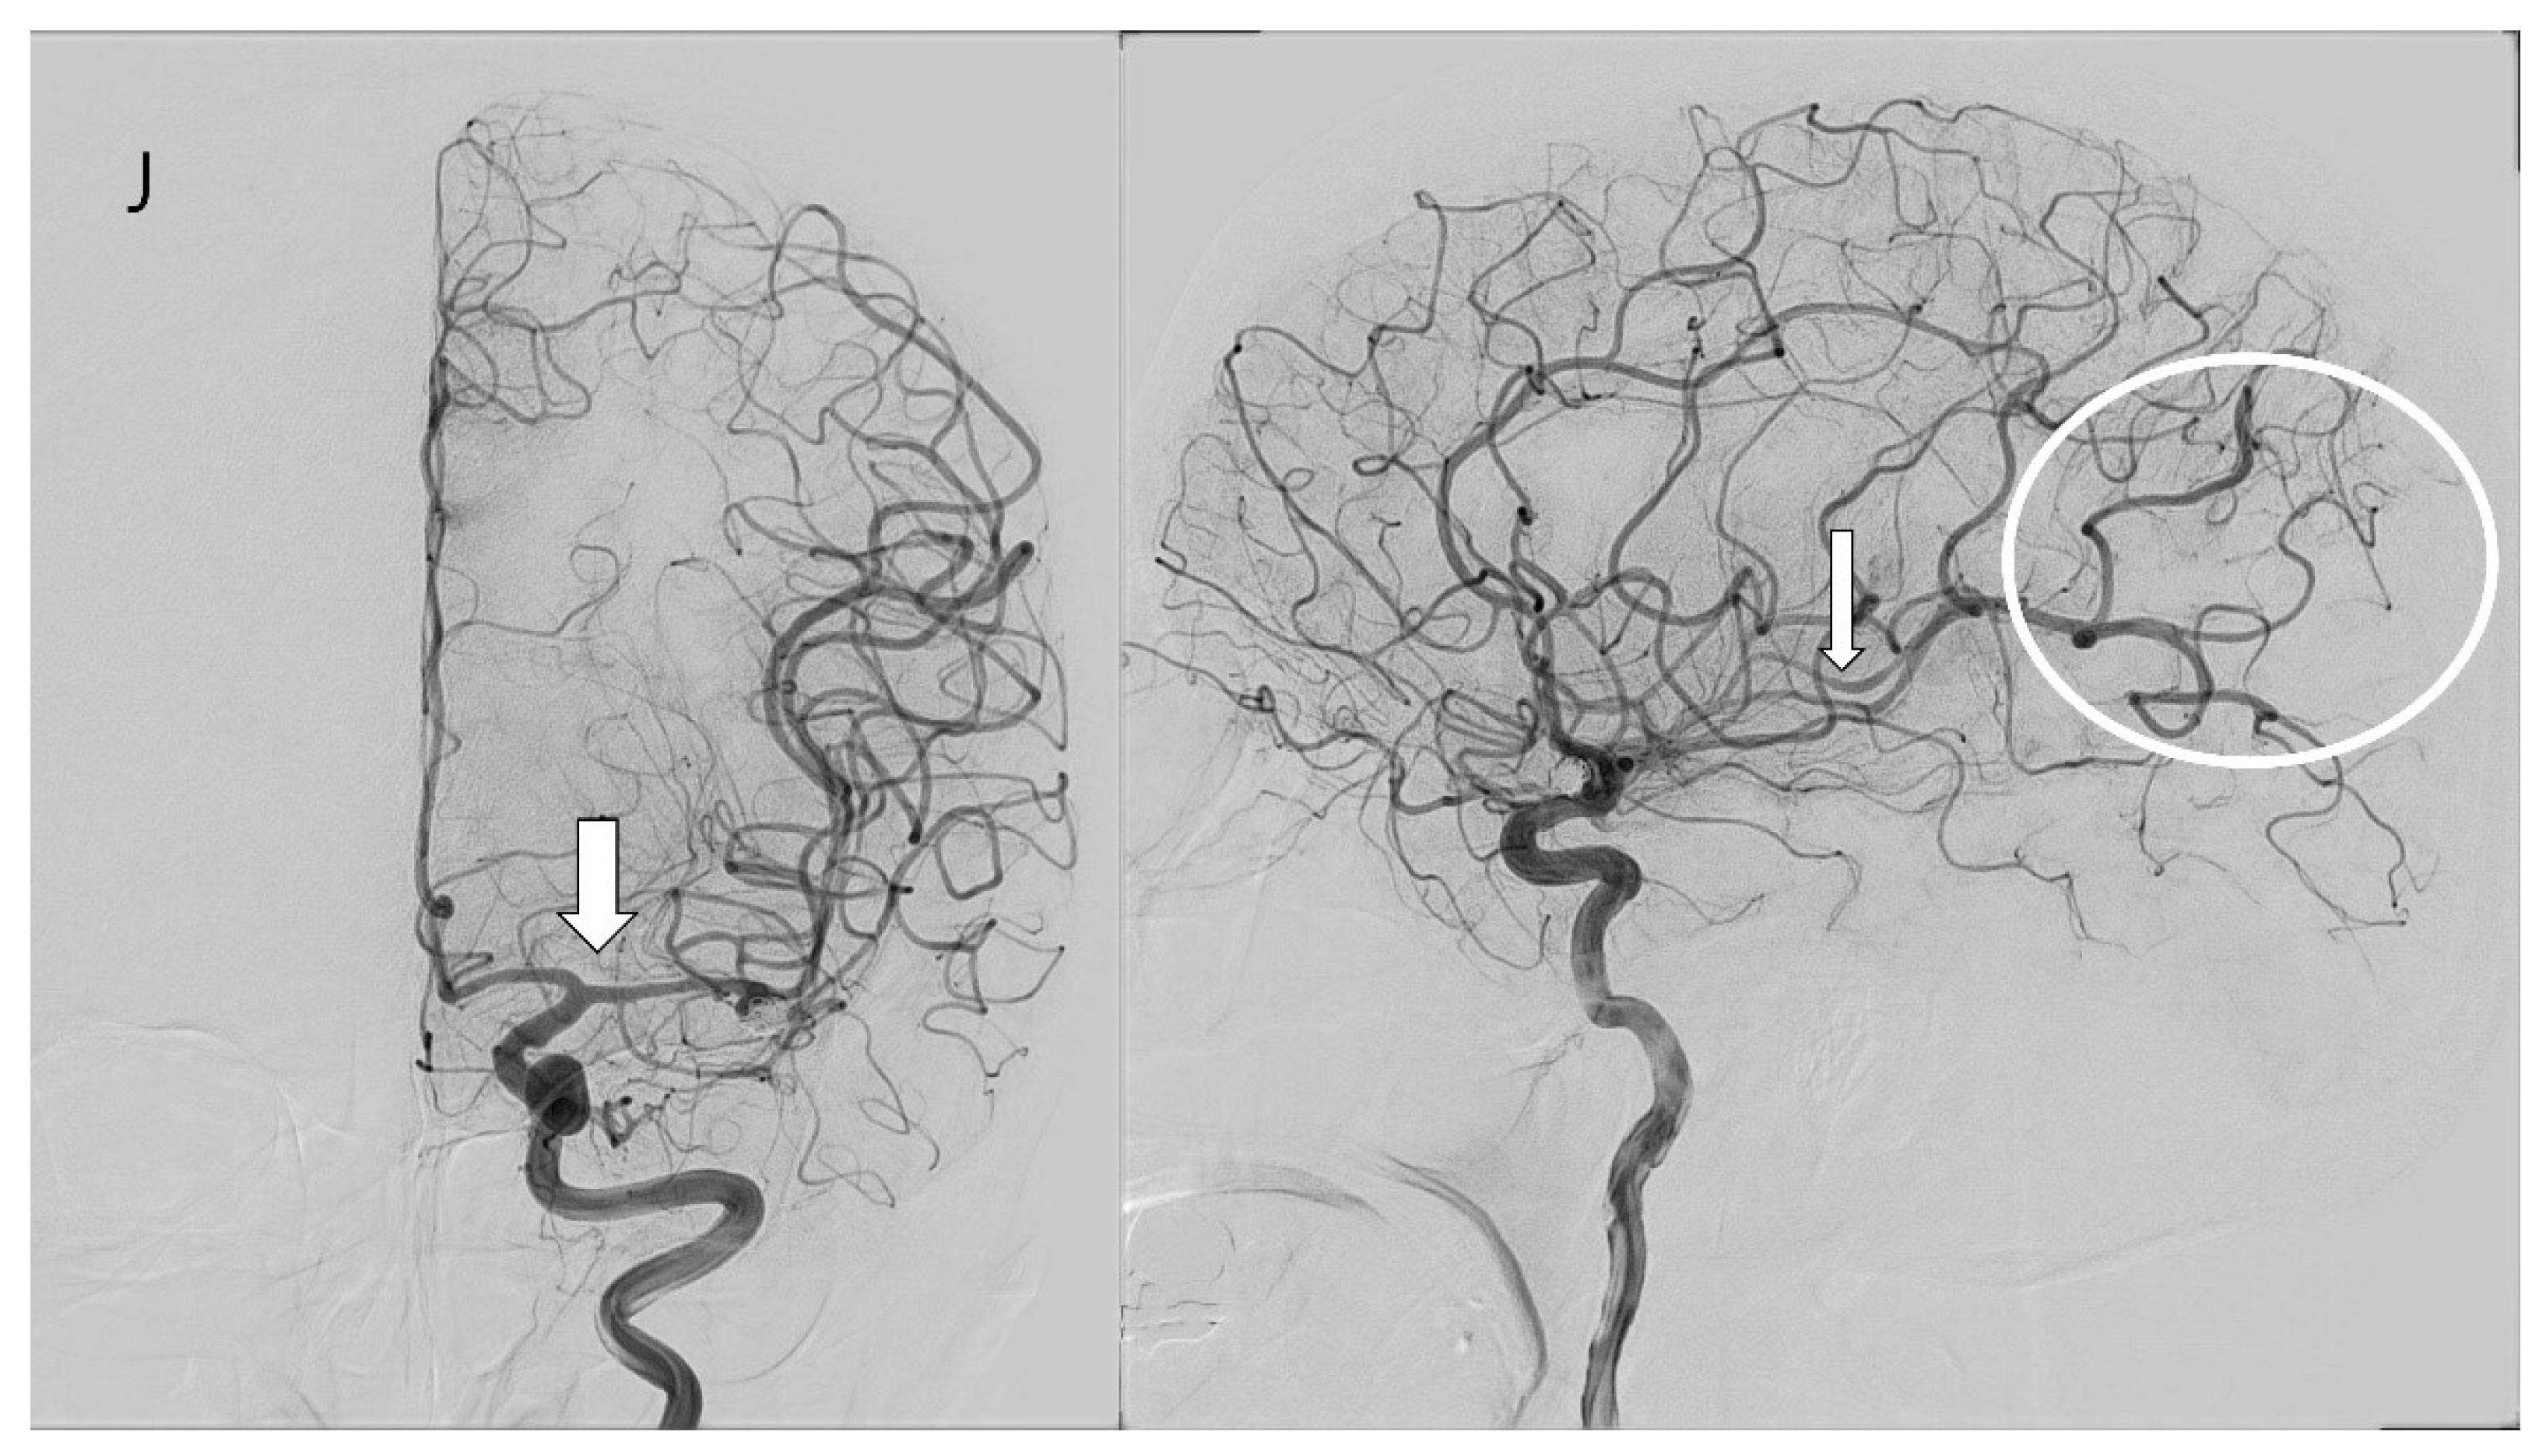

3.4. Case Illustration